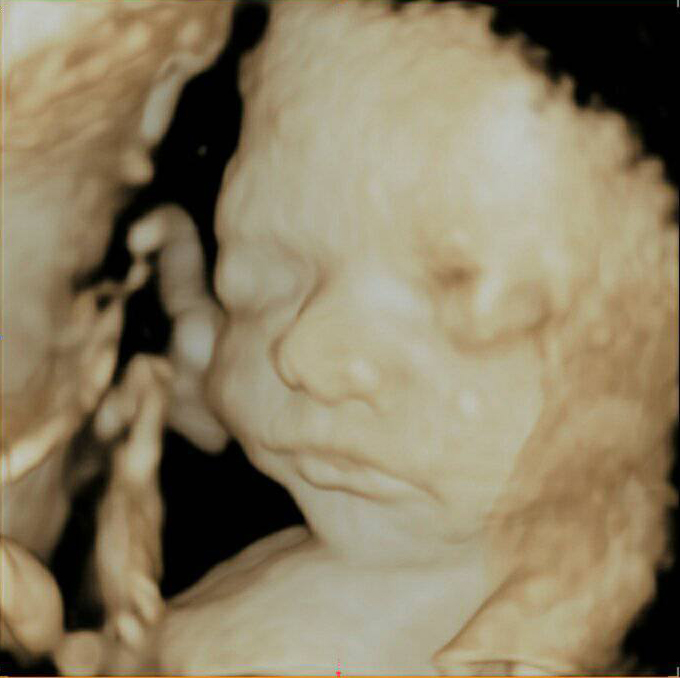

3D i 4D tehnologija omogućava da vidimo površinu bebe na lepši način i pokrete ploda u realnom vremenu.

Takođe nam omogućava da bolje vidimo fetalne mane na licu, šakama i stopalima.

Kao i 2D, 3D i 4D koriste ultrazvučni talas da se kreira slika bebe u materici. 3D je kreirana slika u prostoru dok 4D prikazuje pokret unutar materice pa možemo videti kako se beba smeje, mršti ili zeva.

Da bi se dobile dobre slike poželjno je da se pregled radi između 24 i 32 nedelje trudnoće.